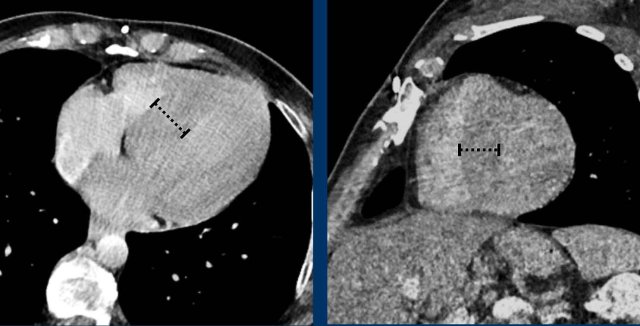

This image is of a female trauma patient, who presented with an intracranial hemorrhage.

Image

Incidentally found severely dilated left ventricle.

The transverse LV diameter is > 70 mm.

Concentric left ventricular hypertrophy in chronic hypertension measuring up to 26 mm at the basal septum.

This is abnormal even in systole.